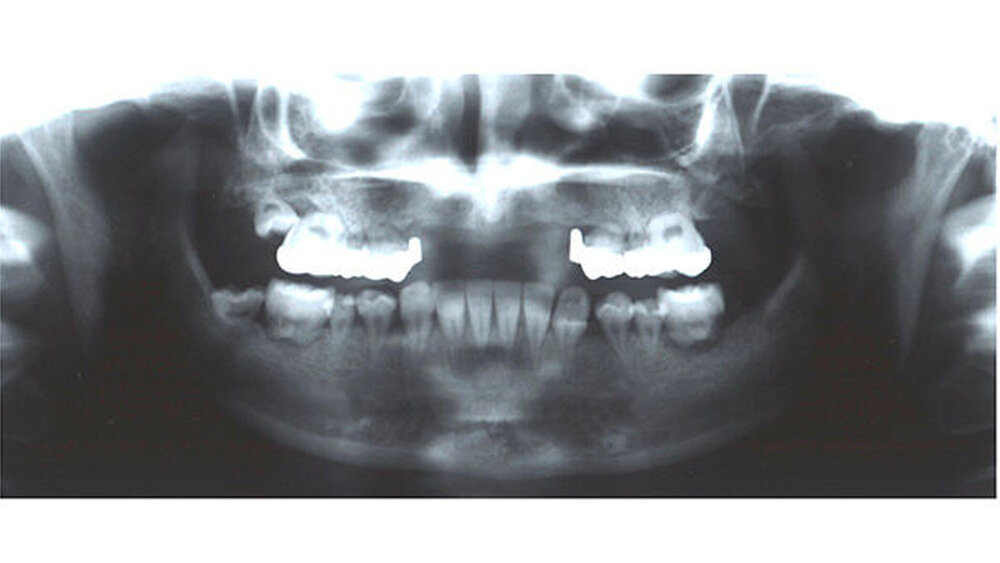

Bereits 1999 wurde in der Oberkieferfront eine extrem aufwendige Augmentation mit Knochen vom Beckenkamm und anschließende Implantation im Frontzahnbereich (regio 13 bis 23) durchgeführt, da es aufgrund der Vorerkrankung zum Verlust der Zähne und des Knochens kam. Zusätzlich war das Weichgewebe durch die Bestrahlung vorgeschädigt.

Trotz dieser Extrembedingungen gelang es dem erfahrenen Stuttgarter MKG-Chirurgenteam um Prof. Dieter Weingart durch Anhebung des Nasenbodens und Einbringung von Eigenknochen in dieser Region ein Fundament für eine neue Zahnversorgung mit Implantaten zu schaffen. Über die Jahre konnten die Seitenzähne zunächst gehalten werden. Im Laufe der Zeit zeigte sich aber, dass die Wurzeln nur noch auf dem Zahnfleisch auf lagen und lediglich durch eine Verblockung der Zähne hielten.